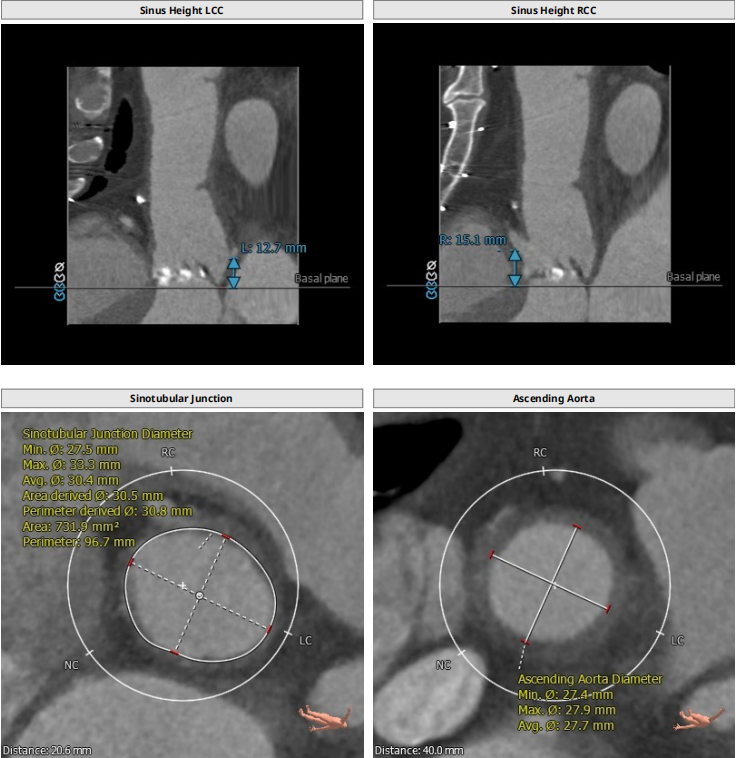

解剖上,这个患者虽然是右无融合的二叶瓣,但是右窦发育较小,形态上接近0型二叶瓣,瓣上钙化中,且集中在左窦,接近左右瓣叶联合部。瓣环及流出道平面较大,而瓣上结构较小,瓣叶联合部距离只有26,这种情况下只能考虑根据瓣上结构进行选择瓣膜。目标瓣膜为26号,为了避免破坏瓣上结构,我们选择26瓣膜的下限20号瓣膜进行与扩张。因为主动脉弓和升主动脉角度问题,没有选择plus。20球囊扩张可以看到左窦钙化很硬,右无联合可以推开,没有反流,故选择26号瓣膜,高位释放。释放后瓣膜下滑到标准位,有明显的腰,故用20球囊进行后扩展。最后造影虽然有中度瓣周漏,但是考虑患者狭窄解除,且升主动脉人工血管限制了瓣膜的流出端,未再行瓣中瓣。术中撤除ECMO,辅助循环约1小时。

患者既往行全升主人工血管置换,为type1型二叶瓣畸形患者,瓣环28.7,左室流出道30.2,二叶瓣鱼嘴短径为26.6,重度钙化,左右冠分别为12.7与15.1,STJ30.8,升主均径人工血管为27.7,患者EF值极低,心功能极差,遂行ECMO辅助下TAVR术式。